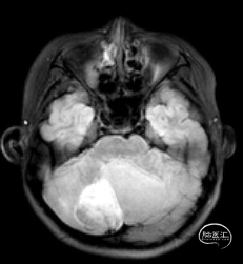

术前MRI

现病史:患者18个月前无明显诱因出现间断头痛,休息后可缓解,开始未予重视,未行特殊治疗。1周前患者无明显诱因出现恶心、呕吐,就诊于当地医院,行颅脑MRI提示:小脑囊实性占位性病变,首先考虑毛细胞星型细胞瘤。现患者为求进一步治疗就诊于我院,门诊以“脑肿瘤”收入院。患者自发病以来神志清,精神可,饮食睡眠正常,二便如常,体重未见明显下降。

小脑肿瘤(毛细胞型星形细胞瘤?)